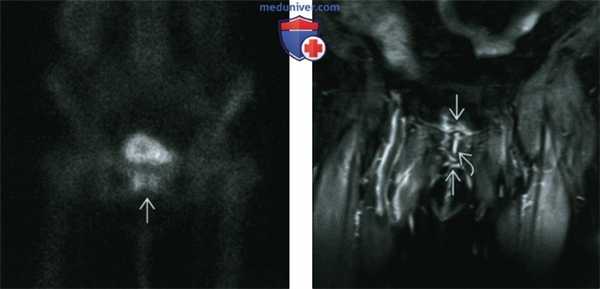

(Слева) МРТ Т1ВИ, аксиальный срез: определяется зрелая костная ткань, расположенная в мягких тканях, окружающих тазобедренный сустав и характеризующаяся сигналом от костного мозга, схожим с сигналом от бедренной кости. Ближе к центру расположена область низкой интенсивности сигнала.

(Справа) МРТ Т2ВИ, аксиальный срез: у этого же пациента спереди от скопления жидкости определяется зрелая кость. Следует помнить, что у пациентов с неврологическими расстройствами, в частности параплегией, высок риск развития ГО, особенно вокруг тазобедренных суставов. В центральной зоне зрелых гетеротопических костных образований может содержаться жидкость. (Слева) МРТ Т1ВИ, корональный срез: на томограмме, полученной при исследовании пациента с параплегией и декубитальной язвой в области крестца, в мягких тканях определяется область низкой интенсивности сигнала, ведущая к конфлюэнтной области низкой интенсивности сигнала в подвздошной кости. Конфлюэнтная, а не дымчатая, область низкой интенсивности сигнала на Т1 ВИ позволяет с уверенностью предполагать остеомиелит, а не ответную реакцию костного мозга. Обратите внимание на мышечную атрофию.

(Справа) МРТ, постконтрастное Т1 ВИ, корональный срез: у этого же пациента определяется контрастирование мягких тканей и бугристости подвздошной кости. Абсцедирование не выявляется, но по результатам биопсии был подтвержден остеомиелит. (Слева) Рентгенография в ПЗ проекции: у этою пациента с параплегией определяется воздух в мягких тканях, что обусловлено хронической декубитальной язвой в подвздошной области. Наблюдается чистый край по ходу подвздошной кости после хирургического удаления инфицированной ранее кости.